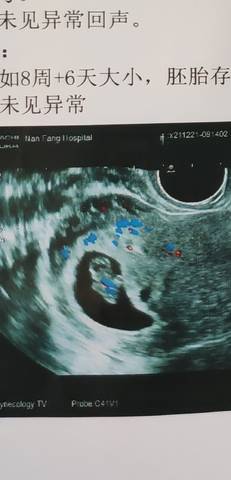

这个娃,怎么脐带在后面啊,这个是属于在子宫哪里呀,请问各位仙女们!

亲爱的,这个看的不是很清楚呀,我是觉得只要目前医生描述的是好的话都没有关系的哈。

那个结果上面来看,我不知道明白是什么意思,这个情况下是属于一个正常的位置,就没啥问题的呀